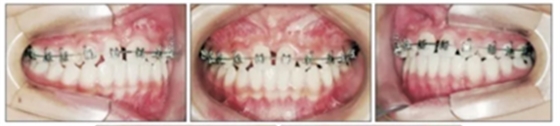

第三階段(圖7,表2)

19歲2月時行固定矯治排齊下頜牙列建立穩(wěn)定的咬合及正常的覆合覆蓋,持續(xù)1年10月。摘除后(21歲)上下頜用固定保持器,上頜牙弓用Hawley保持器。